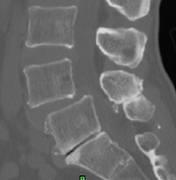

据悉,腰椎管狭窄症是指各种原因引起椎管变窄,压迫硬膜囊、脊髓或神经根,从而导致相应神经功能障碍的一类疾病。腰椎滑脱症是指某个腰椎的椎体相对与邻近的腰椎向前滑移,即为腰椎滑脱,它们是导致腰痛及腰腿痛等常见腰椎病的病因之一,多发于40岁以上的中年人。随着现代生活习惯、节奏的改变,腰椎退变所致的腰椎管狭窄症和腰椎滑脱症患者越来越多,严重威胁广大患者的生活质量。

misTLIF手术是近年来发展起来的一项骨科新技术,主要用于腰椎管狭窄症、腰椎滑脱症。它与传统的开放手术相比,有着明显优势,术中切口小,创伤出血少,且无需广泛切开肌肉韧带等软组织,避免了因肌肉软组织剥离过多而导致的迟发性脊柱不稳;由于手术创伤小,术后患者恢复快,可以尽早下床活动,减少了术后切口感染以及卧床时间过长带来的一系列并发症。